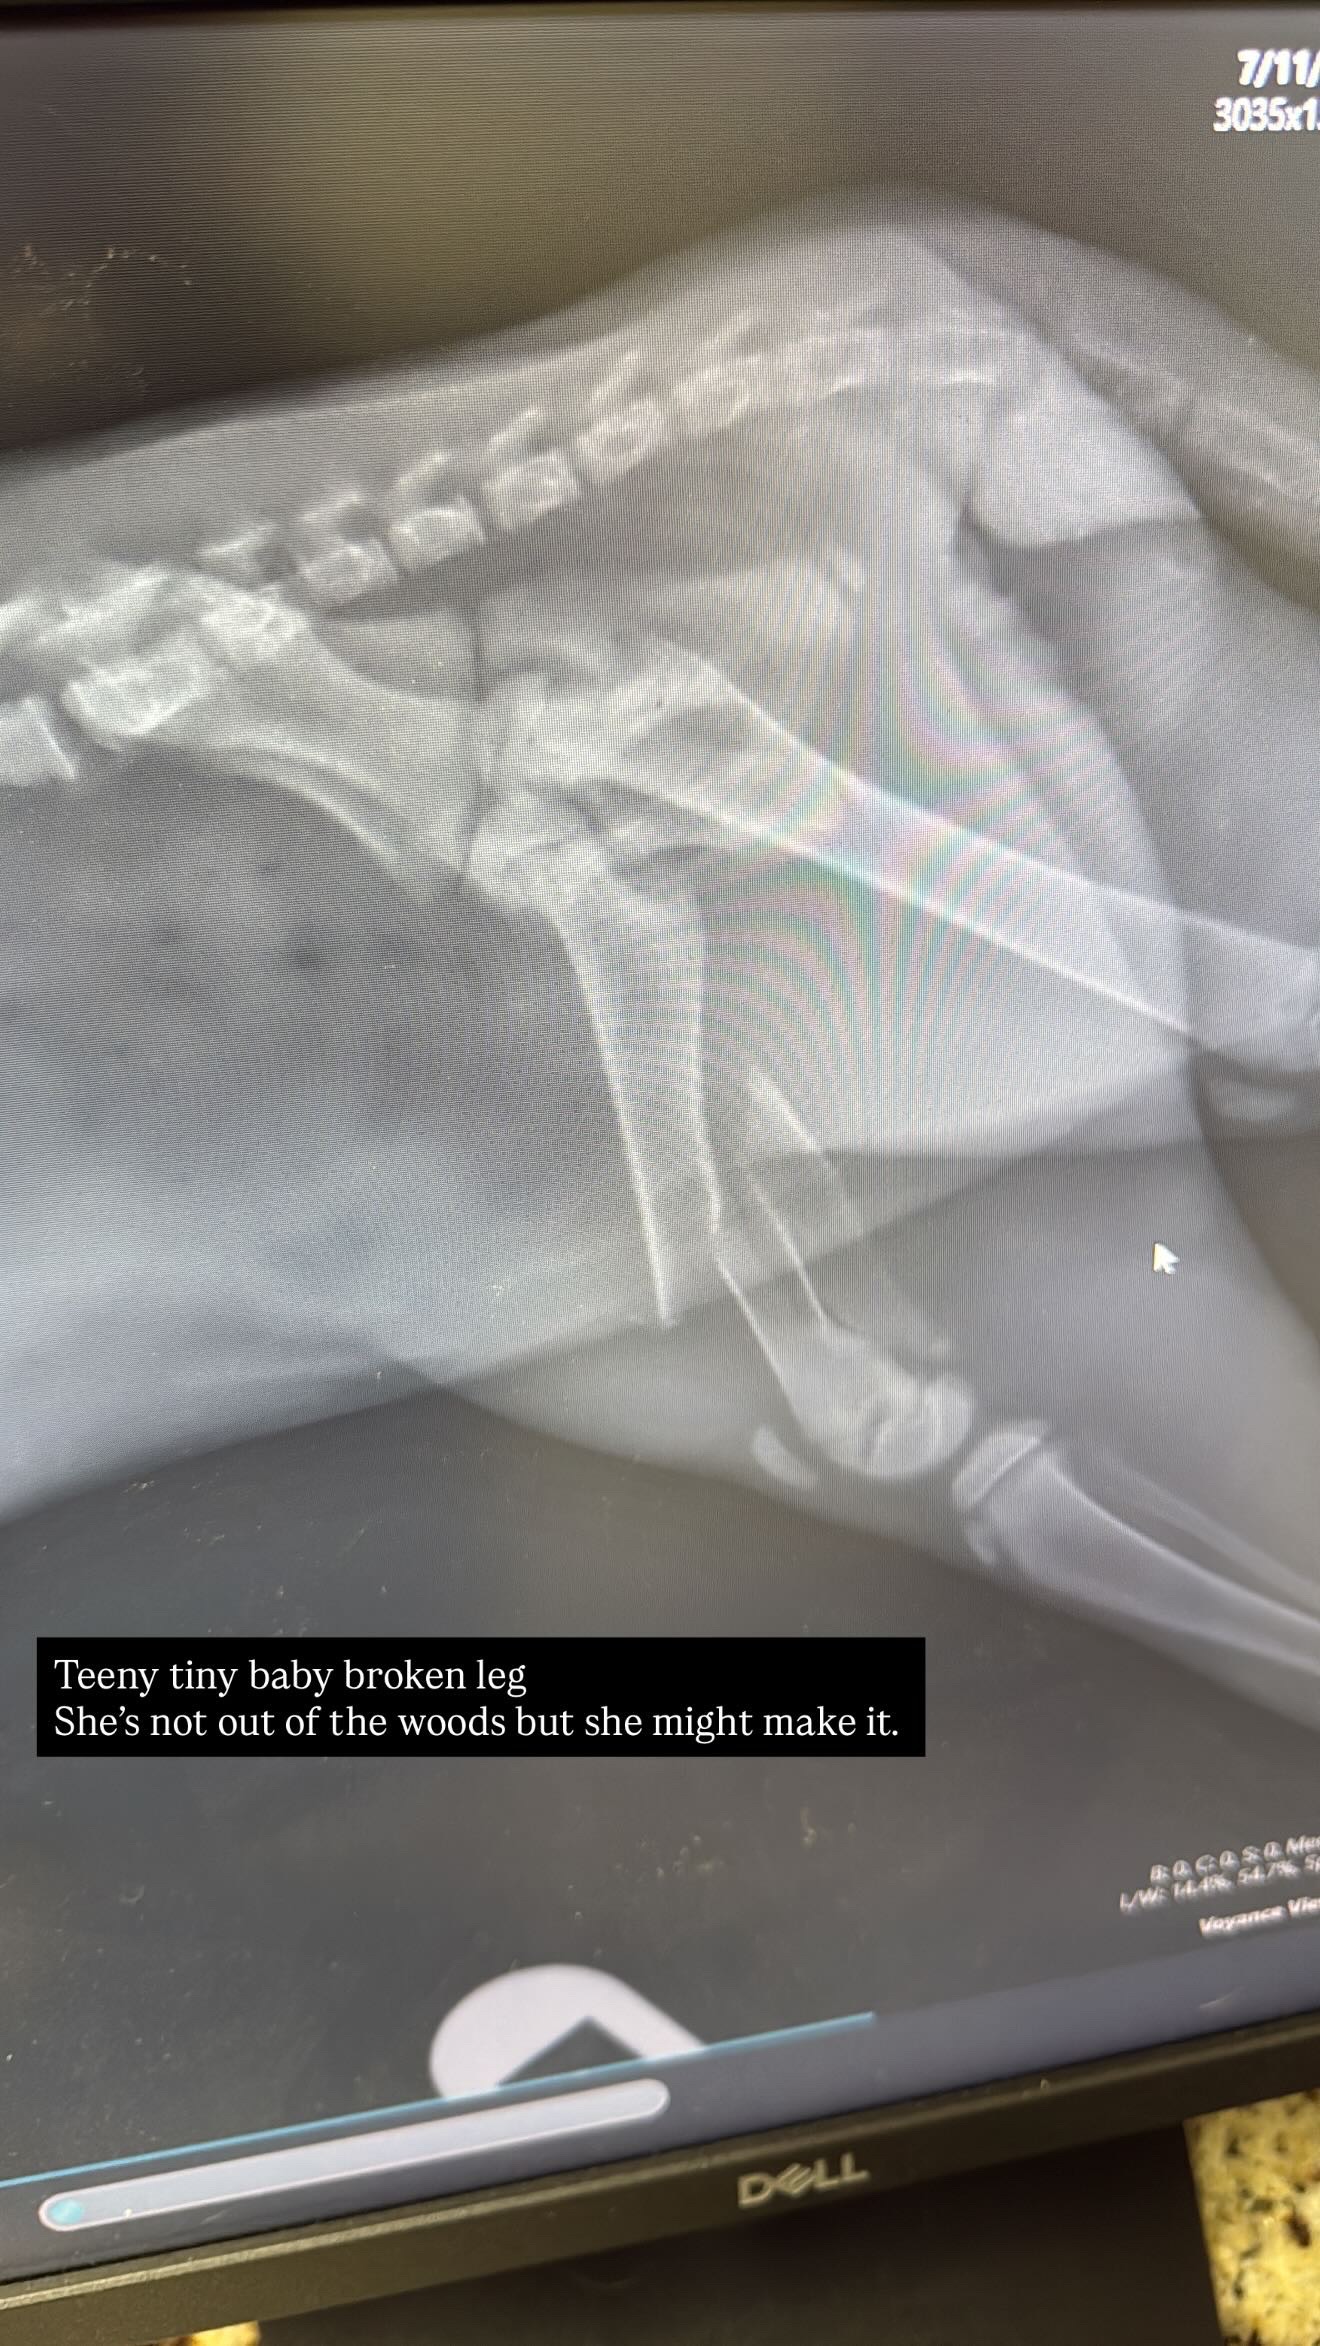

This little 6 week old kitten was hit by a car outside of my house. I was able to get to her and take her to a vet to be seen for any further help or possible end of life procedures depending on her condition. She ended up passing away after initial treatment and testing. I’m left with the bills from trying to help her recover. Anything helps. Thank you.